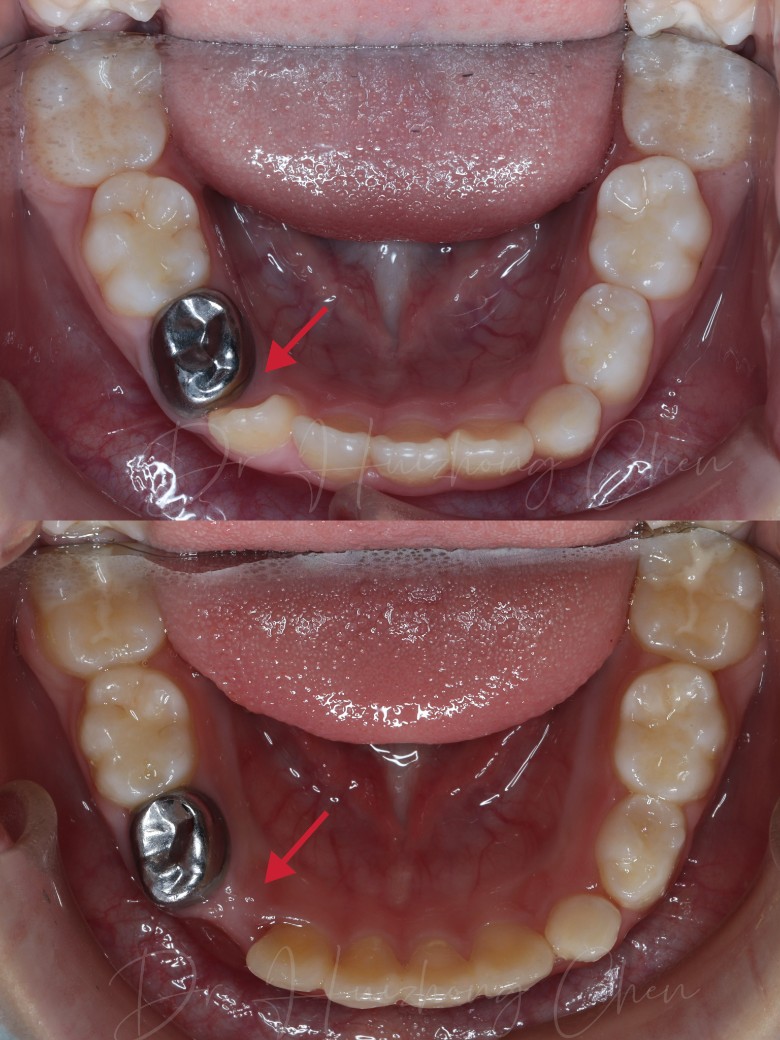

前面戴了不到一年的牙套吧,改善的还不错, 中场休息戴一段时间的保持器等换几颗牙再开始下一步方案,没空长牙的间隙肉眼可见的拉出来了,长歪的牙也拉的正正的了熊孩子配合的也不错,一天到晚除了吃饭都乖乖戴着,戴了这么久只丢过一副牙套,唯一的槽点就是刷牙太敷衍了,每次去都要被医生教育一下刷牙认真认真再认真点

还是蛮整齐的

现在看着蛮整齐的